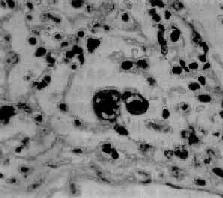

腺病毒肺炎

图9-21 腺病毒肺炎

图中央可见肿大肺泡上皮细胞中的核内包含体

早期或轻型病毒性肺炎表现为间质性肺炎,炎症从支气管、细支气管开始,沿肺间质发展,支气管、细支气管壁及其周围、小叶间隔以及肺泡壁等肺间质充血、水肿,有一些淋巴细胞单核细胞浸润,肺泡壁明显增宽(图9-20)。肺泡腔内一般无渗出物或仅有少量浆液。病变较重者,肺泡也可受累,出现由浆液、少量纤维蛋白、红细胞及巨噬细胞组成的炎性渗出物,甚至可发生组织坏死。有些病毒性肺炎(如流感病毒肺炎,麻疹病毒肺炎、腺病毒肺炎等)肺泡腔内渗出较明显,渗出物浓缩凝结成一层红染的膜样物贴附于肺泡内表面,即透明膜形成。支气管上皮的肺泡上皮也可增生,甚至形成多核巨细胞。麻疹病毒肺炎的病变特点为在间质性肺炎的基础上,肺泡壁上有透明膜形成,并有较多的多核巨细胞(巨细胞肺炎),在增生的上皮细胞和多核巨细胞的胞浆内和胞核内可检见病毒包含体。病毒包含体常呈球形,约红细胞大小,呈嗜酸性染色,均质或细颗粒状,其周围常有一清晰的透明晕。其他一些病毒性肺炎也可在增生的支气管上皮、支气管粘液腺上皮或肺泡上皮细胞内检见病毒包含体。如腺病毒肺炎可在增生的上皮细胞核内(图9-21),呼吸道合胞病毒肺炎可在增生的上皮细胞胞浆内,巨细胞病毒肺炎也可在增生的上皮细胞核内检见病毒包含体。检见包含体是病理组织学诊断病毒性肺炎的重要依据。